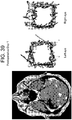

- Scatterplots of the entire time series were created by plotting the 100,000 (x,y) pairs representing the two orthogonal components of the instantaneous angle of pupil reflection over time to create 'box trajectories' that reflected the temporal nature of the pupillary movement.

- these figures look like boxes, reflecting the timing of the aperture as it moved around the screen ( Figure 20 ).

- the raw data is preprocessed as follows: for the x (horizontal) and y (vertical) vectors independently, the mean is subtracted and divided by the standard deviation (which is the square root of the variance). This puts all the data in the same relative frame (zero-mean, max and min about 1 and -1). This is the reason the boxes look square (even if the stimulus presentation monitor is not square).

- a patient without a known IIIrd palsy, but with a history of inferior orbital wall fracture resulting in transient diplopia five years prior also had decreased vertical amplitude on eye-tracking ( Figure 20 , bottom row).